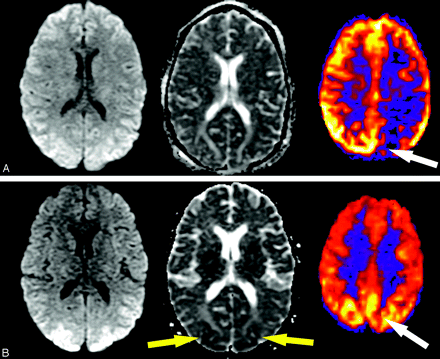

PRES and PRES-like syndromes can occur spontaneously or in association with uncontrolled hypertension, eclampsia, and cyclosporine toxicity and as a complication of certain chemotherapeutic regimens.14–16 A loss of autoregulatory control occurs in these syndromes, and initial attempts to maintain perfusion pressure result in arteriolar vasoconstriction. Hyperperfusion follows and results in reversible edema, more commonly in the vertebrobasilar vascular territories likely because of the relatively fewer perivascular sympathetic nerves in this area.14 Figure 11 demonstrates changes with time in a 31-year-old patient with PRES, including initial vasoconstriction and hypoperfusion followed by rebound hyperperfusion. ASL is a robust technique in the evaluation of hyperperfusion syndromes due to its repeatability and its strength in depicting high-flow states. Figure 12 demonstrates a case of post-endarterectomy hyperperfusion syndrome in a patient who had recently undergone ipsilateral carotid endarterectomy. This is a well-described phenomenon using other perfusion techniques17 and is presumed to result from loss of autoregulatory function.

Evolution of perfusion changes in PRES in a 31-year-old woman. A, Initial images: high signal intensity on the initial diffusion-weighted image (left) represents T2 shinethrough secondary to edema seen on the apparent diffusion coefficient (ADC) images (center) in the occipital cortices. A corresponding ASL map (right) reveals marked flow asymmetry with hypoperfusion in the left occipital lobe (white arrow). B, At 2-week follow-up, diffusion and ADC images show new posterior restricted diffusion (yellow arrows), and bilateral hyperperfusion is now evident on perfusion images (right, white arrow).